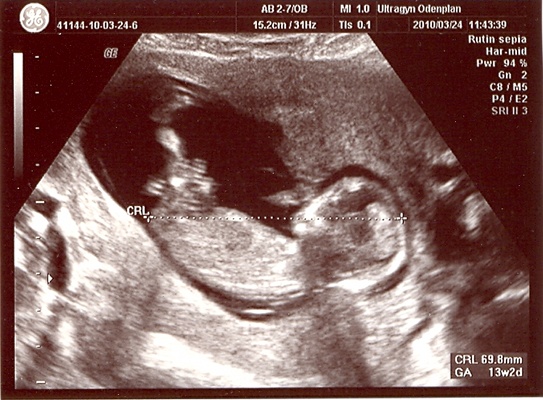

It’s official: we’re expecting another baby! ETA around September 28th.

Many congratulations to you and Eric! My wife (Sarah) gave birth to twin girls last October. Seeing your picture reminds me of our first scan. It was quite a shock!